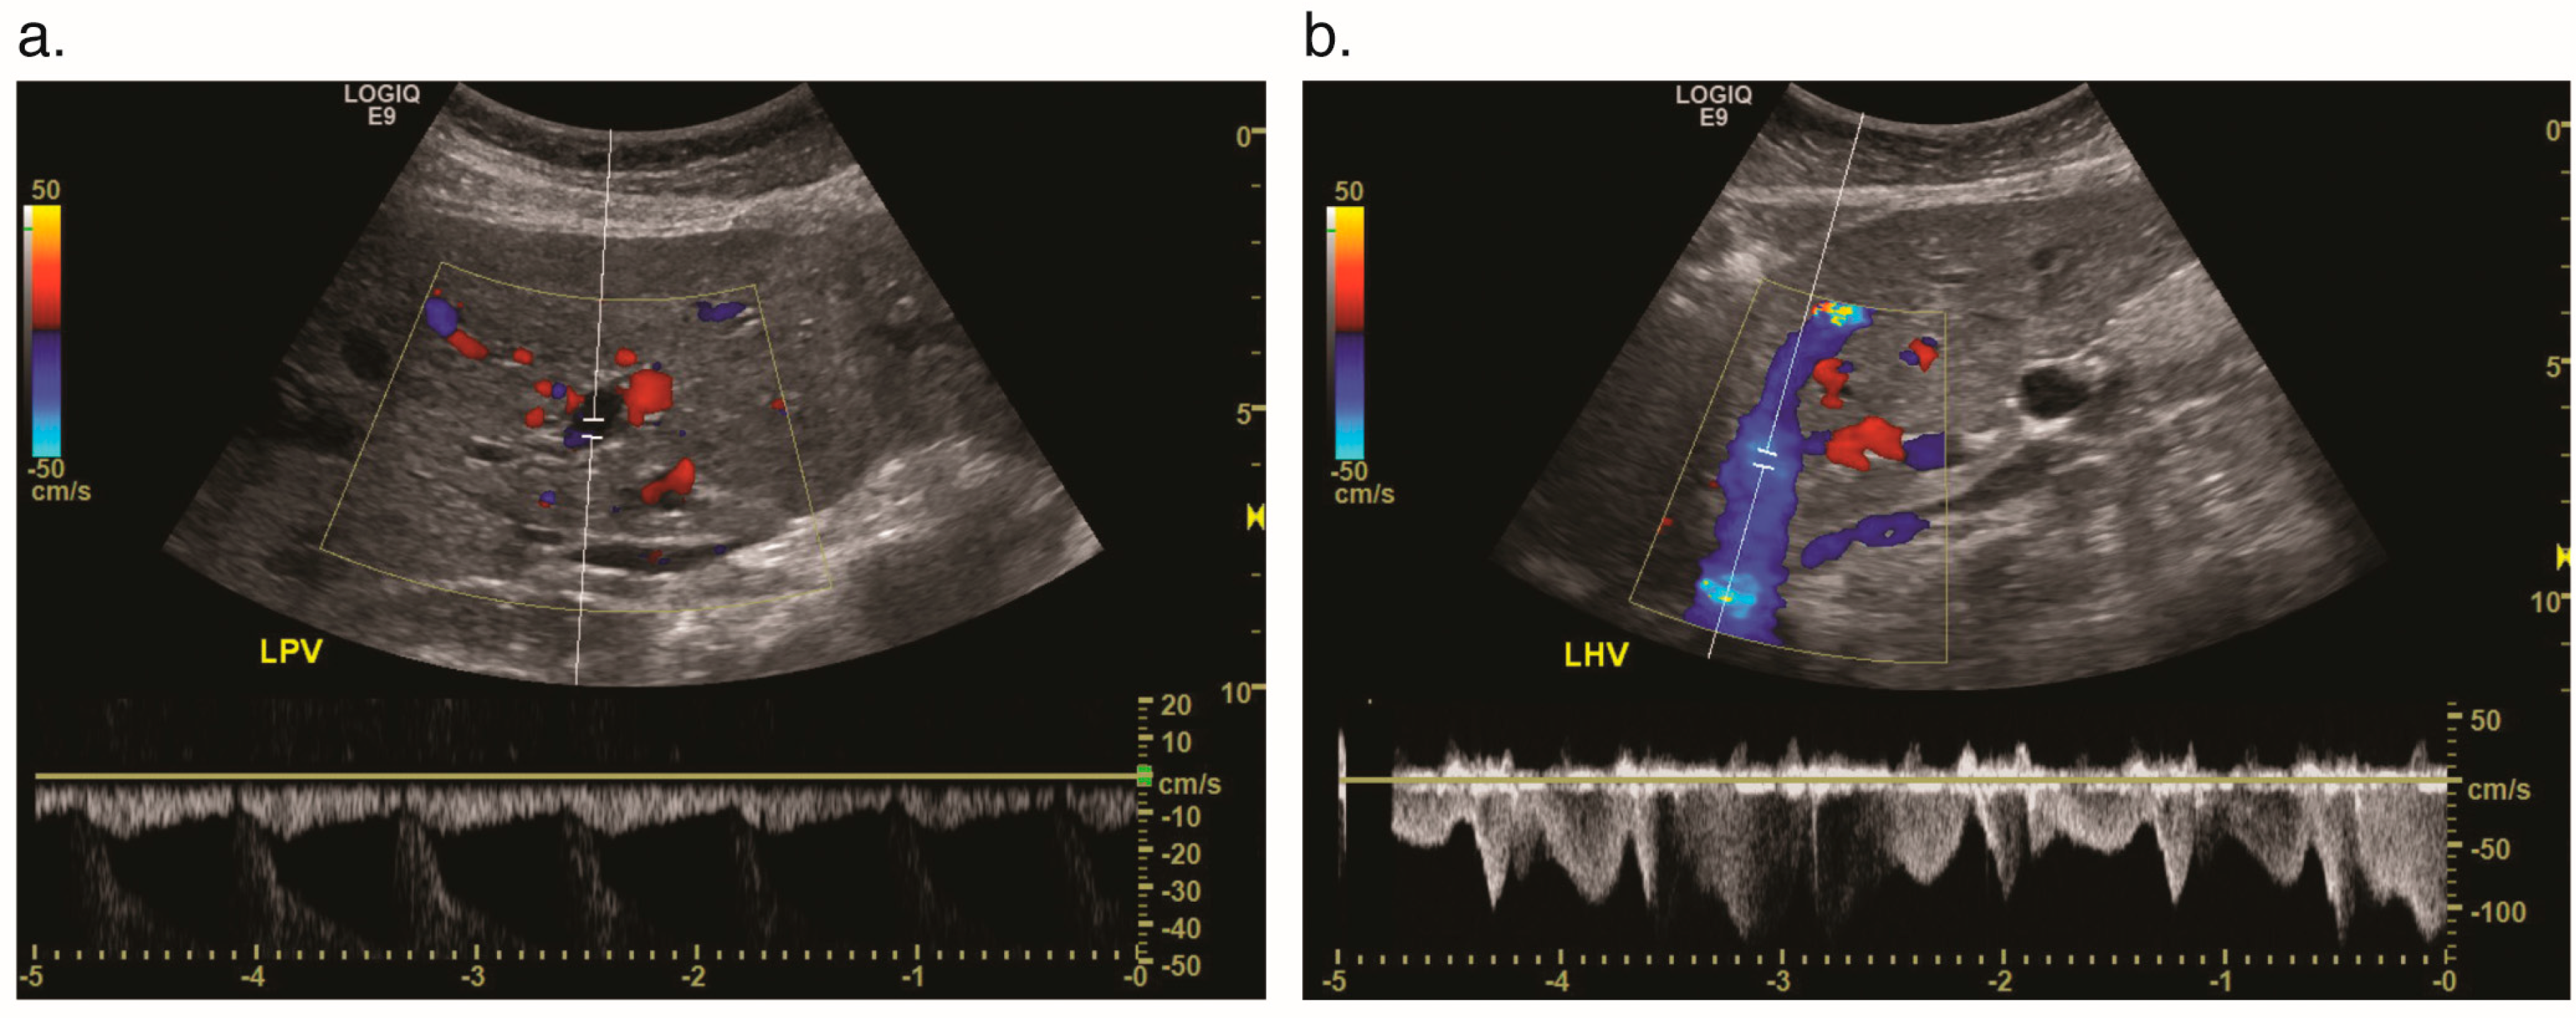

4.1. Ultrasound